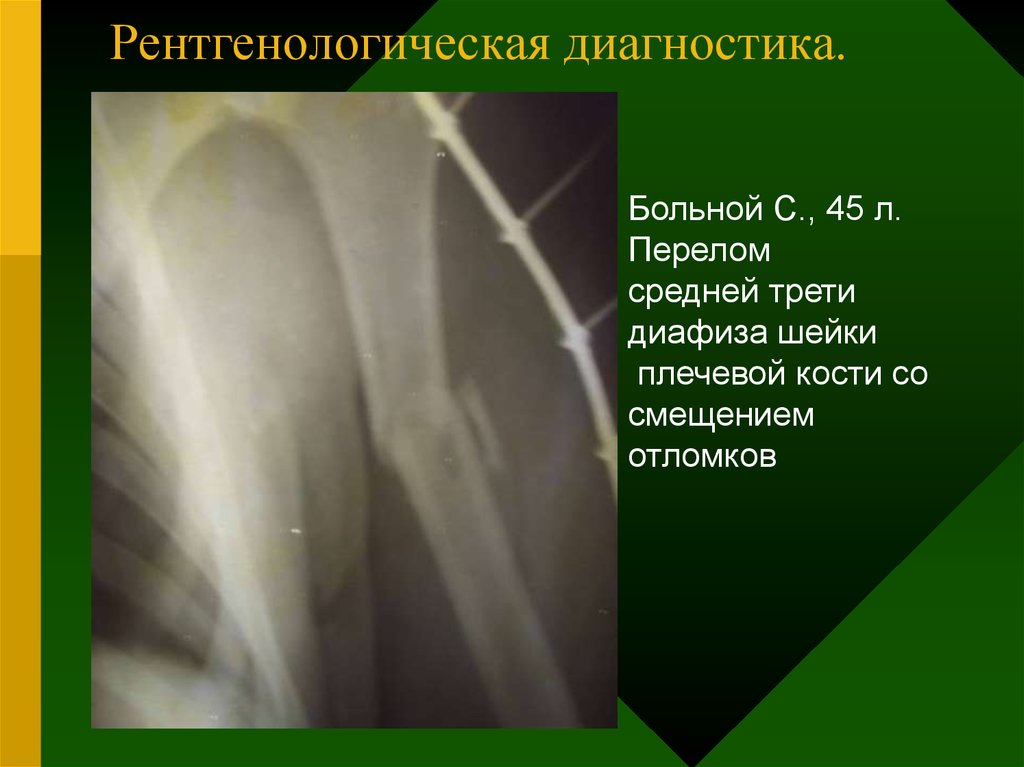

Классификация переломов диафиза бедренной кости: Иллюстрации и информация